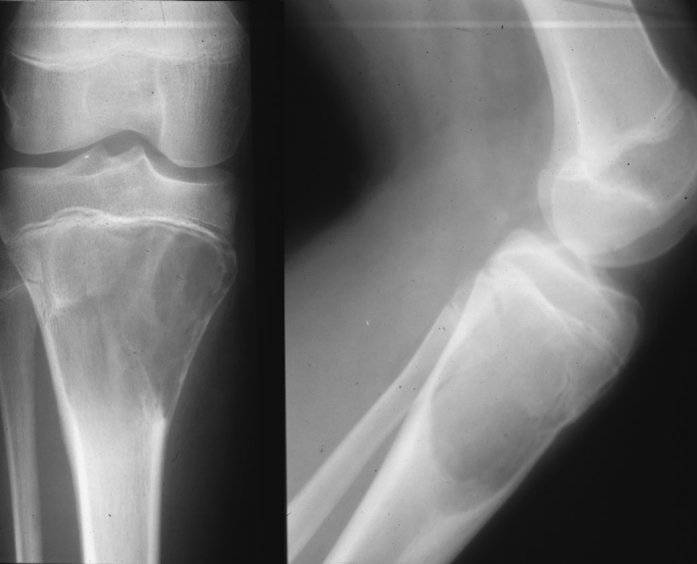

Düz Grafi

Kemik şikayeti olan her hastaya öncelikli olarak düz grafi çekilir. Değişik kemik patolojilerinde (rahatsızlıklarında) her hastalığa özgü değişik görüntüler çıkar ve bunlar değerlendirilir. Kemik patolojileri; osteoartirit (kireçlenme), osteoporoz (kemikte erime), kemik tümörleri, kemikte oluşan kırıklar ve çatlaklar şeklinde sıralanabilir. Bazı rahatsızlıklarda düz grafi yeterli iken, bazı rahatsızlıklarda ileri tetkikler yapmak gerekir.